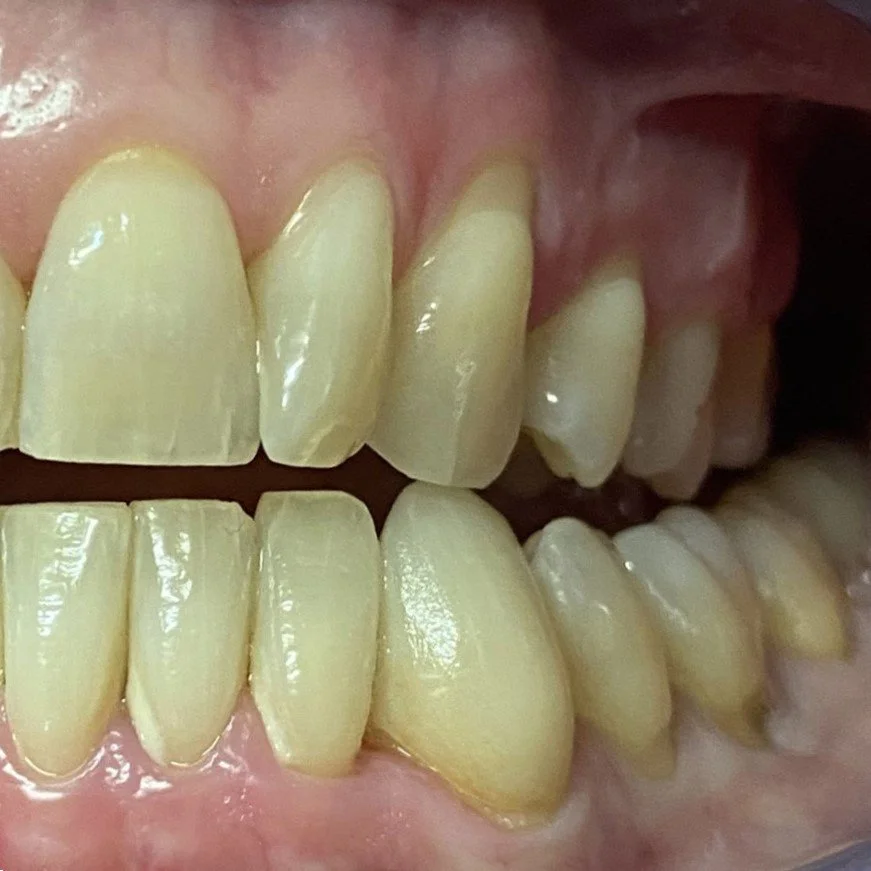

A TMJ Disorder patient requires conservative management with “Full Occlusal Therapy” in 3 stages along with concurrent Full Counselling (refer to journal papers 19 and 20).  In other words, we need to get the disc back into the centre of the joint where it belongs starting with Full Counselling and then a Fully Protective Occlusal Splint (Stage 1).  This splint is made of acrylic resin (used for dentures) and can be made in clear resin but is usually coloured blue or pink to hide any future discolouration (as in the photos below). The splint usually fits the upper teeth and only one is required.

CASE STUDY 1

PROTECTIVE CROWNS FOR BIO-DESIGNING LEFT AND RIGHT JAW MOVEMENTS

CASE STUDY 2

PROTECTIVE COMPOSITE RESIN OVERLAYS FOR BIO-DESIGNING LEFT AND RIGHT JAW MOVEMENTS